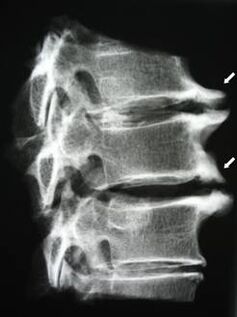

In the early stages, osteochondrosis is detected by MRI.Later, the pathology can be diagnosed by x-ray.On x-rays of the cervical spine, a decrease in the distance between the vertebrae, pathological changes in the facet joints and osteophytosis become noticeable.

| Cervical osteochondrosis | The appearance of pathological changes in one or more segments of movement of the spine.Impaired spinal mobility, development of myofascial pain syndromes and spinal root pinching | Pain, paresthesia and motor disturbances in the cervical region, which spread to the back of the head and upper limbs.Detection of characteristic changes in the spine on MRI and X-rays (osteophytes, decrease in the distance between the vertebrae, signs of damage to the intervertebral joints) |